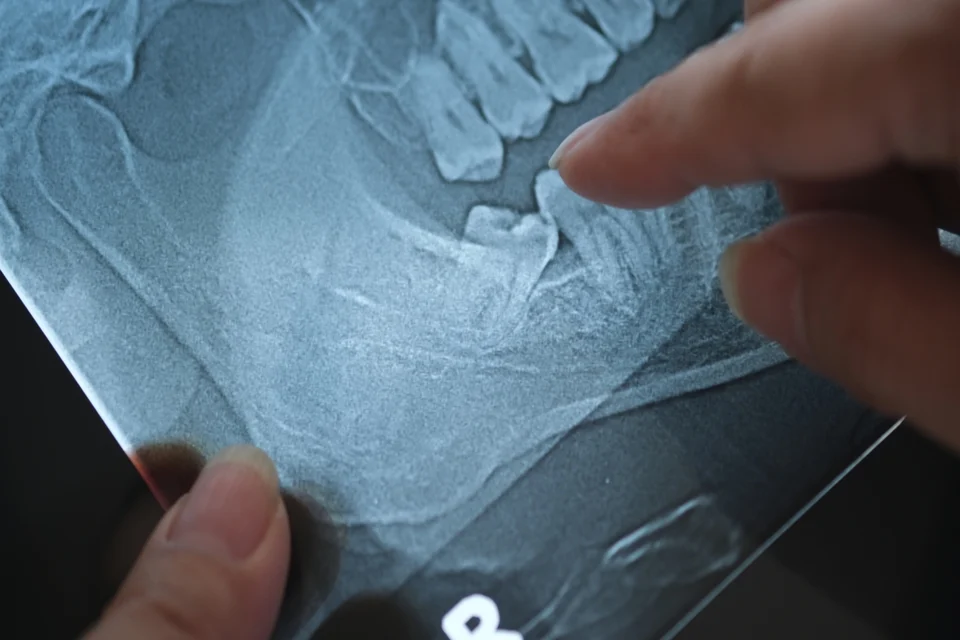

顧名思義,根尖手術是針對牙根尖端進行處理,而顯微根尖手術則是在牙科顯微鏡輔助下完成,讓整個治療過程在更高倍率與充足光源中進行,以下整理顯微根尖手術的主要操作流程:

- 定位病灶並清除感染組織:透過顯微鏡觀察骨頭與牙根位置,精準找到根尖與病灶範圍,將感染與壞死組織徹底清除。

- 切除根尖並進行逆向清創:將牙根尖約3mm切除後,利用超音波器械從根管末端逆向清潔內部,確保細菌來源被完整處理。